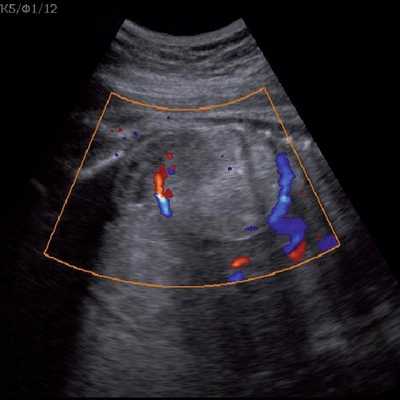

Под диафрагмой справа визуализировалось гиперэхогенное опухолевидное образование несколько неоднородной солидной структуры, с четкими ровными контурами, размером 50x38x35 мм. К нижнему полюсу данного образования прилежала правая почка, имеющая нормальные размеры, форму и структуру. Нижняя полая вена была смещена кпереди и влево. Обращала на себя внимание выраженная гепатомегалия, причем структура печени не была однородной. Она содержала множественные гиперэхогенные включения размерами до 17 мм, окруженные тонким гипоэхогенным периферическим ободком. Цветовое допплеровское картирование(ЦДК) демонстрировало интенсивную периферическую васкуляризацию опухоли (рис. 1-3).

Рис. 1. Нейробластома правого надпочечника плода. Беременность 31 нед 4 дня.

Рис. 2. Кровоток в нейробластоме плода. Цветовое допплеровское картирование. Отчетливо виден питающий сосуд, огибающий образование по его периферии. К нижнему полюсу образования прилежит интактная почка плода.